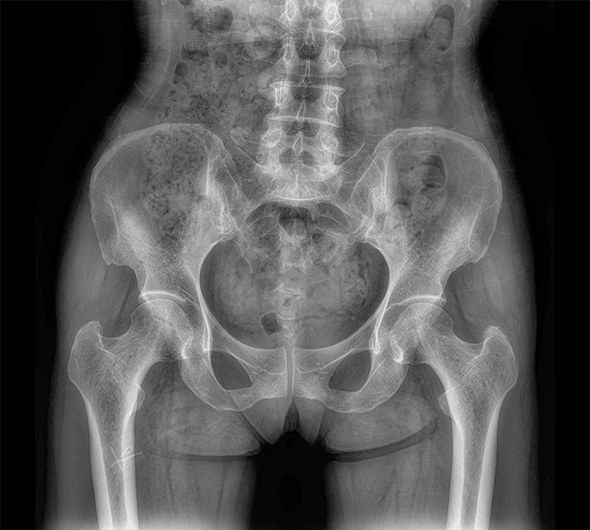

原厂优质影像链,搭载直接生长式碘化铯非晶硅平板,带来更加清晰锐利的图像效果。